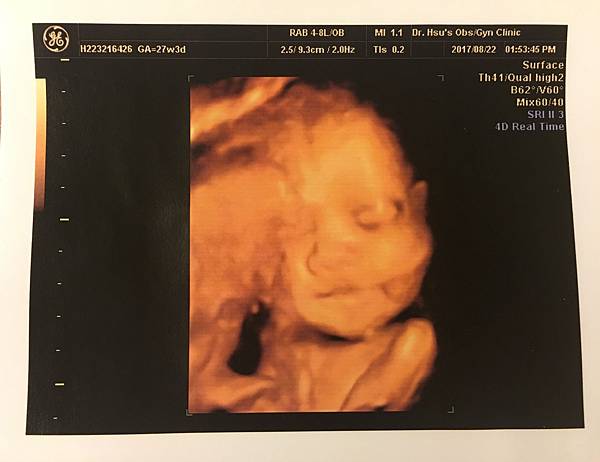

27週 自費4D立體超音波

這個基本上就是娛樂性質大於產檢性質啦

超期待可以看到4D的皮妞

照之前有好好跟她說,她也超乖乖配合

剛開拍1分鐘就微笑了

(雖然拍到後面他就不想配合了覺得有完沒完吧)

天啊,我的寶貝在對我們微笑![]()

這看起來應該比較像媽媽吧哈哈

生命真的好奧妙,妳從一個小米粒長到現在這麼大了